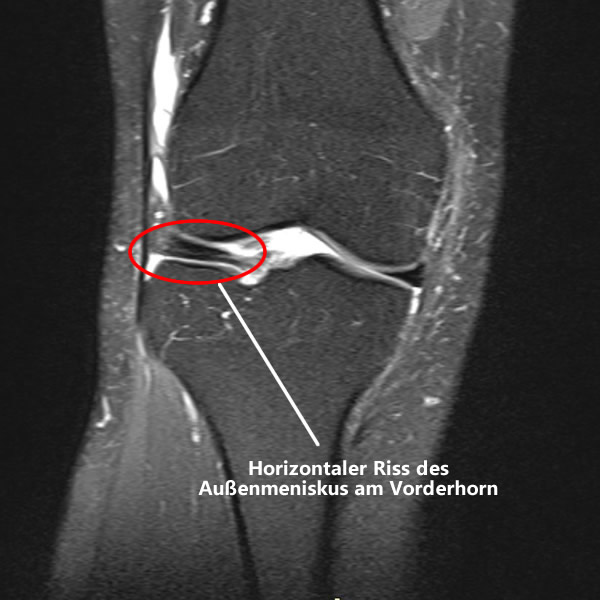

Manchmal braucht es nur einen falschen Schritt, um alle Pläne über den Haufen zu werfen. Bei meiner Fehmarn-Umrundung passierte genau das. Ein unglücklicher Tritt, ein Meniskusriss am Vorderhorn des Außenmeniskus. Eine ziemlich seltene Verletzung, wie sich herausstellen sollte. Details zu diesem Unfall habe ich dir nachfolgend verlinkt. Die Kurzfassung: Mein Knie war im Eimer und damit auch mein Gendarmstien-Traum.

Die Diagnose: Meniskusriss am Vorderhorn

Der Orthopäde und Kniespezialist schaute sich die Bilder mit mehreren Kollegen an – so unauffällig war der Riss zunächst. Doch dann kam die Empfehlung zur Operation.